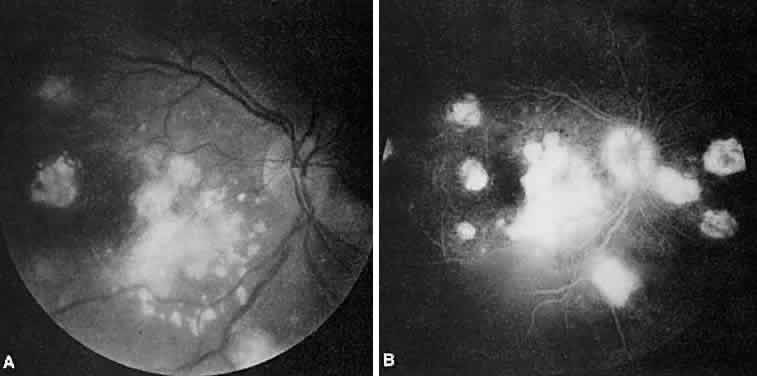

Multifocal choroiditis may mimic the typical clinical findings of presumed ocular histoplasmosis syndrome (discussed later) and has the additional finding of anterior chamber and vitreous cells. Multiple yellow or gray acute choroidal lesions measuring 50 to 350 μm, periphlebitis, and occasionally retinal neovascularization can be seen. Marked pigmentary disturbances may be seen in the chronic phase (Fig. 11A).

Fig. 11. Multifocal choroiditis. A. Fundus photograph showing pigmentary disturbances. B. Multiple areas of hypofluorescence and hyperfluorescence representing chorioretinal scars with associated atrophic areas. C. Indocyanine green angiogram shows multiple areas of hypofluorescence around the disc, the macula, and the midperipheral fundus. Some of these areas are not visible clinically or on fluorescein angiogram.

On fluorescein angiography (see Fig. 11B), the punched-out lesions show the typical window defects. Acute lesions block early choroidal fluorescence and stain late. Cystoid macular edema and prolonged arteriovenous circulation times may be seen.39 Progressive subretinal fibrosis is a reported sequela that presents as multiple stellar zones of subretinal fibrosis. This fibrosis can be surrounded by multiple atrophic punched-out lesions (Fig. 12).40

Fig. 12. Multifocal choroiditis with subretinal fibrosis in a 26-year-old woman. A and B. Color photographs show hypopigmented lesions representing subretinal fibrosis involving both macular lesions. Multiple punched-out lesions surround the bands of fibrosis. C. Staining of the large stellate fibrous lesion can be seen in the left macula. There are multiple punched-out lesions above and below the macular zone. Leakage from the optic disc and its vessels can also be seen.

ICG angiography shows large hypofluorescent spots in the posterior pole measuring 200 to 500 μm, which did not usually correspond to clinically or fluorescein angiographically detectable lesions (see Fig. 11C). Smaller hypofluorescent spots, less than 50 μm, also may be seen in the posterior pole. Both large and small lesions are best seen in the later phases of the angiogram. Confluent hypofluorescent areas may be seen around the optic nerve in patients reporting an enlarged blind spot on visual field testing.41